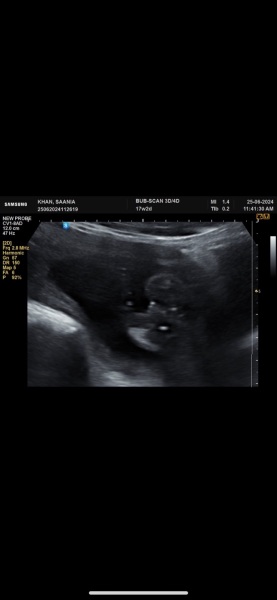

Is this a girl or boy

Potty shot